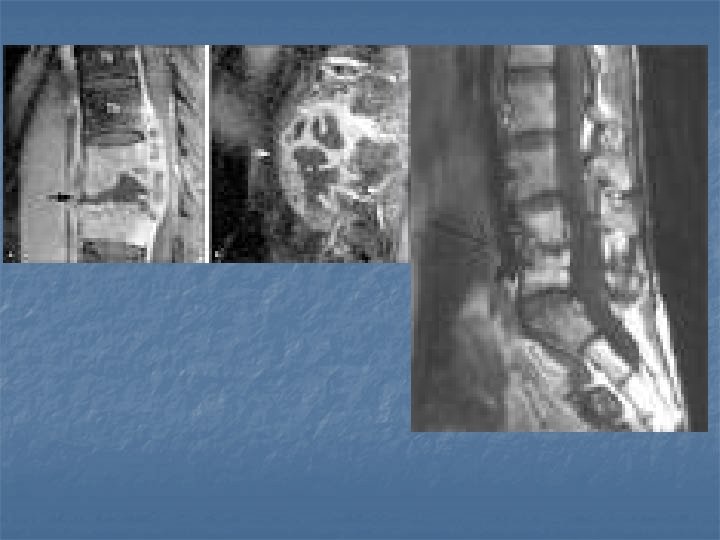

Osteomyelit-1 è Mısır mumyaları (ilk olgu) è Gibbus nedeni (Galen - Hipokrat) è Patolojinin tanımlanması ( Sir Percival Pott 19 yy sonu) è Posterior füzyon ile deformite tedavisi (Hibbs Albee 1911) è 102 olgu - ilk seri - %50 mortalite laminektomi +drenaj (Kulowski 1936) è Laminektomi Kontrendike (Seddon 1936) è Anterior debridman + grefonaj (Hodgson

Osteomyelit- 5 è Kronik dönemde deformite ortaya çıkar è Tanı è Direkt grafi è 3 -6 haftada ilk bulgular (endplate erozyonu, disk mesafesi daralması, korpus vertebrada rarefaksiyon, kifoz eğilimi) è Radyonükleid è Tc 99 scanning pirofosfat ile %80 spesifisite è CT è MR è Etkenler è Staph aureus, pseudomonas (İV madde bağımlıları) , Tbc

Osteomyelit- 6 è Tedavi è erken dönemde saptanan olgularda è mutlak yatak istirahati (ağrı geçinceye değin) è antibiyoterapi ( 8 hafta) è eksternal destek è debridman è ardışık + grefonaj + antibiyoterapi 2 korpus tutulumu è abse formasyonu è korpus vertebrada > %50 yükseklik kaybı